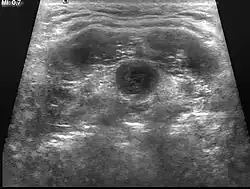

A ultrassonografia cervical faz facilmente o diagnóstico, observando-se cisto simples ou com sinais inflamatórios (dependendo do quadro clínico) na linha mediana da região anterior.